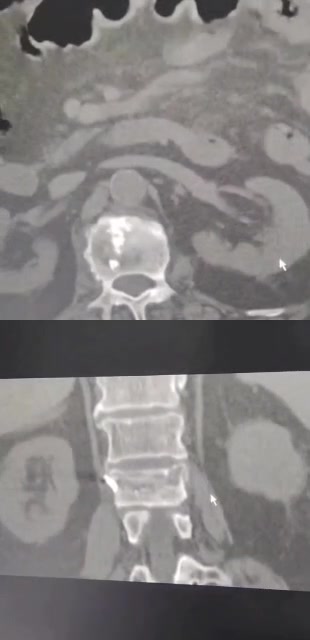

那么看术后CT

可是患者仍感觉腰痛,两个月后去B医院就诊,B医院观点是对侧再次穿刺加注骨水泥,站友们你的观点呢?

据病人描述加注后疼痛缓解

术后